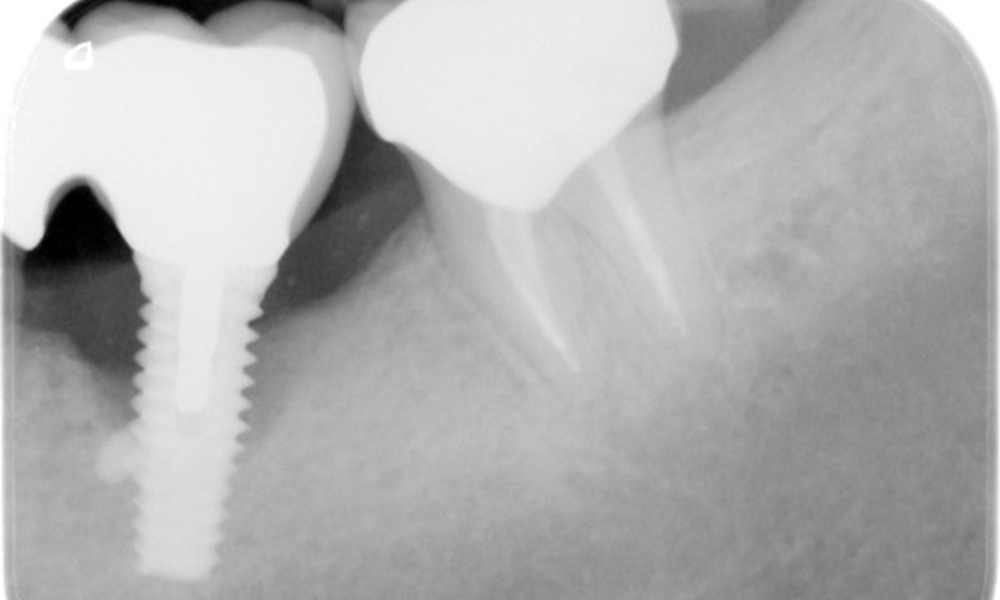

Рентгеновите снимки показват прогресията на костната загуба.

Рентгеновите снимки показват прогресиращата загуба на костна тъкан в областта на импланта в област 36: рентгенова снимка от 11.02.2021 г. (вляво) и рентгенова снимка от 18.01.2024 г. (вдясно).

ОПГ: 26/02/2024 Дентална рентгенова снимка 18/01/2024